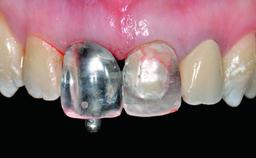

A 32-year-old female Caucasian patient with a compromised maxillary right central incisor was referred to us by a general dentist. Her chief complaints were discomfort and mobility of tooth 11 with unsatisfactory esthetics due to discoloration. The patient reported a previous trauma, some years earlier, as the origin of pathology on the afflicted tooth. Anamnesis was negative for any other dental or periodontal pathology in the remaining dentition. The patient did not take any medication and reported to be a light smoker (5–10 cigs/day). She had high esthetic expectations of her treatment. The extraoral examination revealed a high smile line with full exposure of her maxillary teeth and surrounding soft tissue in the area between the second premolars.

Provisional Implant-Supported Prosthesis Prosthodontic margin > 3 mm apical to mucosal margin Prosthodontic margin > 3 mm apical to mucosal margin

Interim Prosthesis during Healing Fixed Fixed